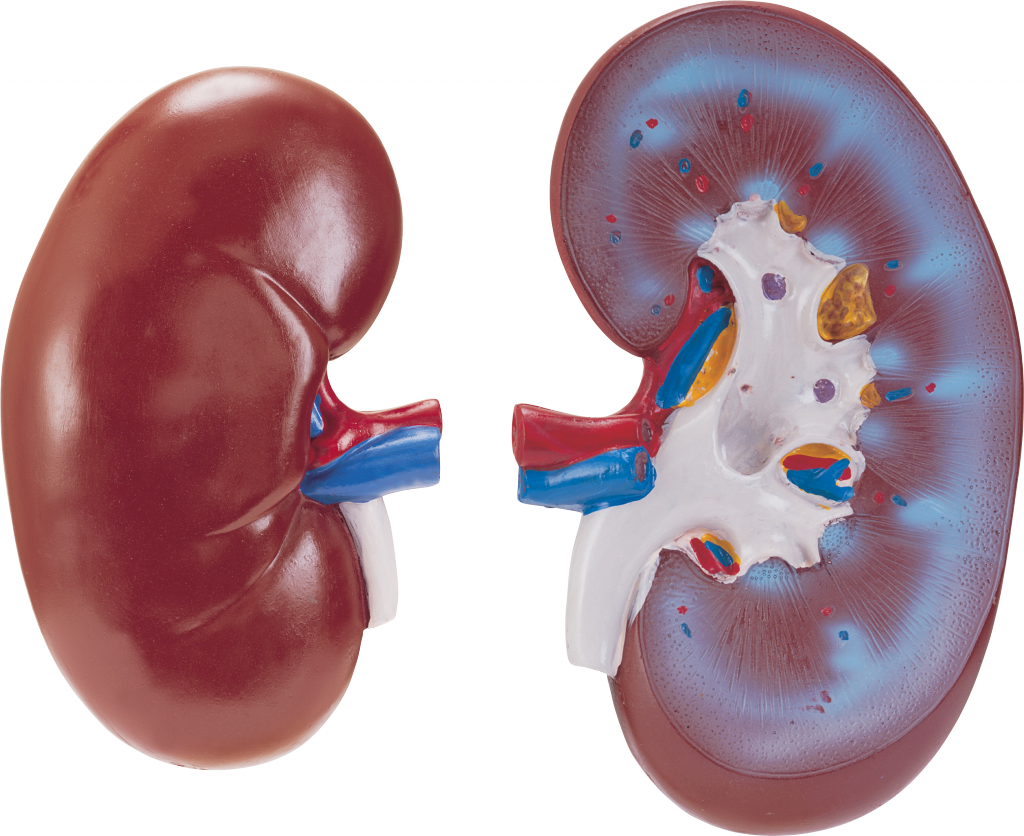

Строение почек человека: Фото и описание